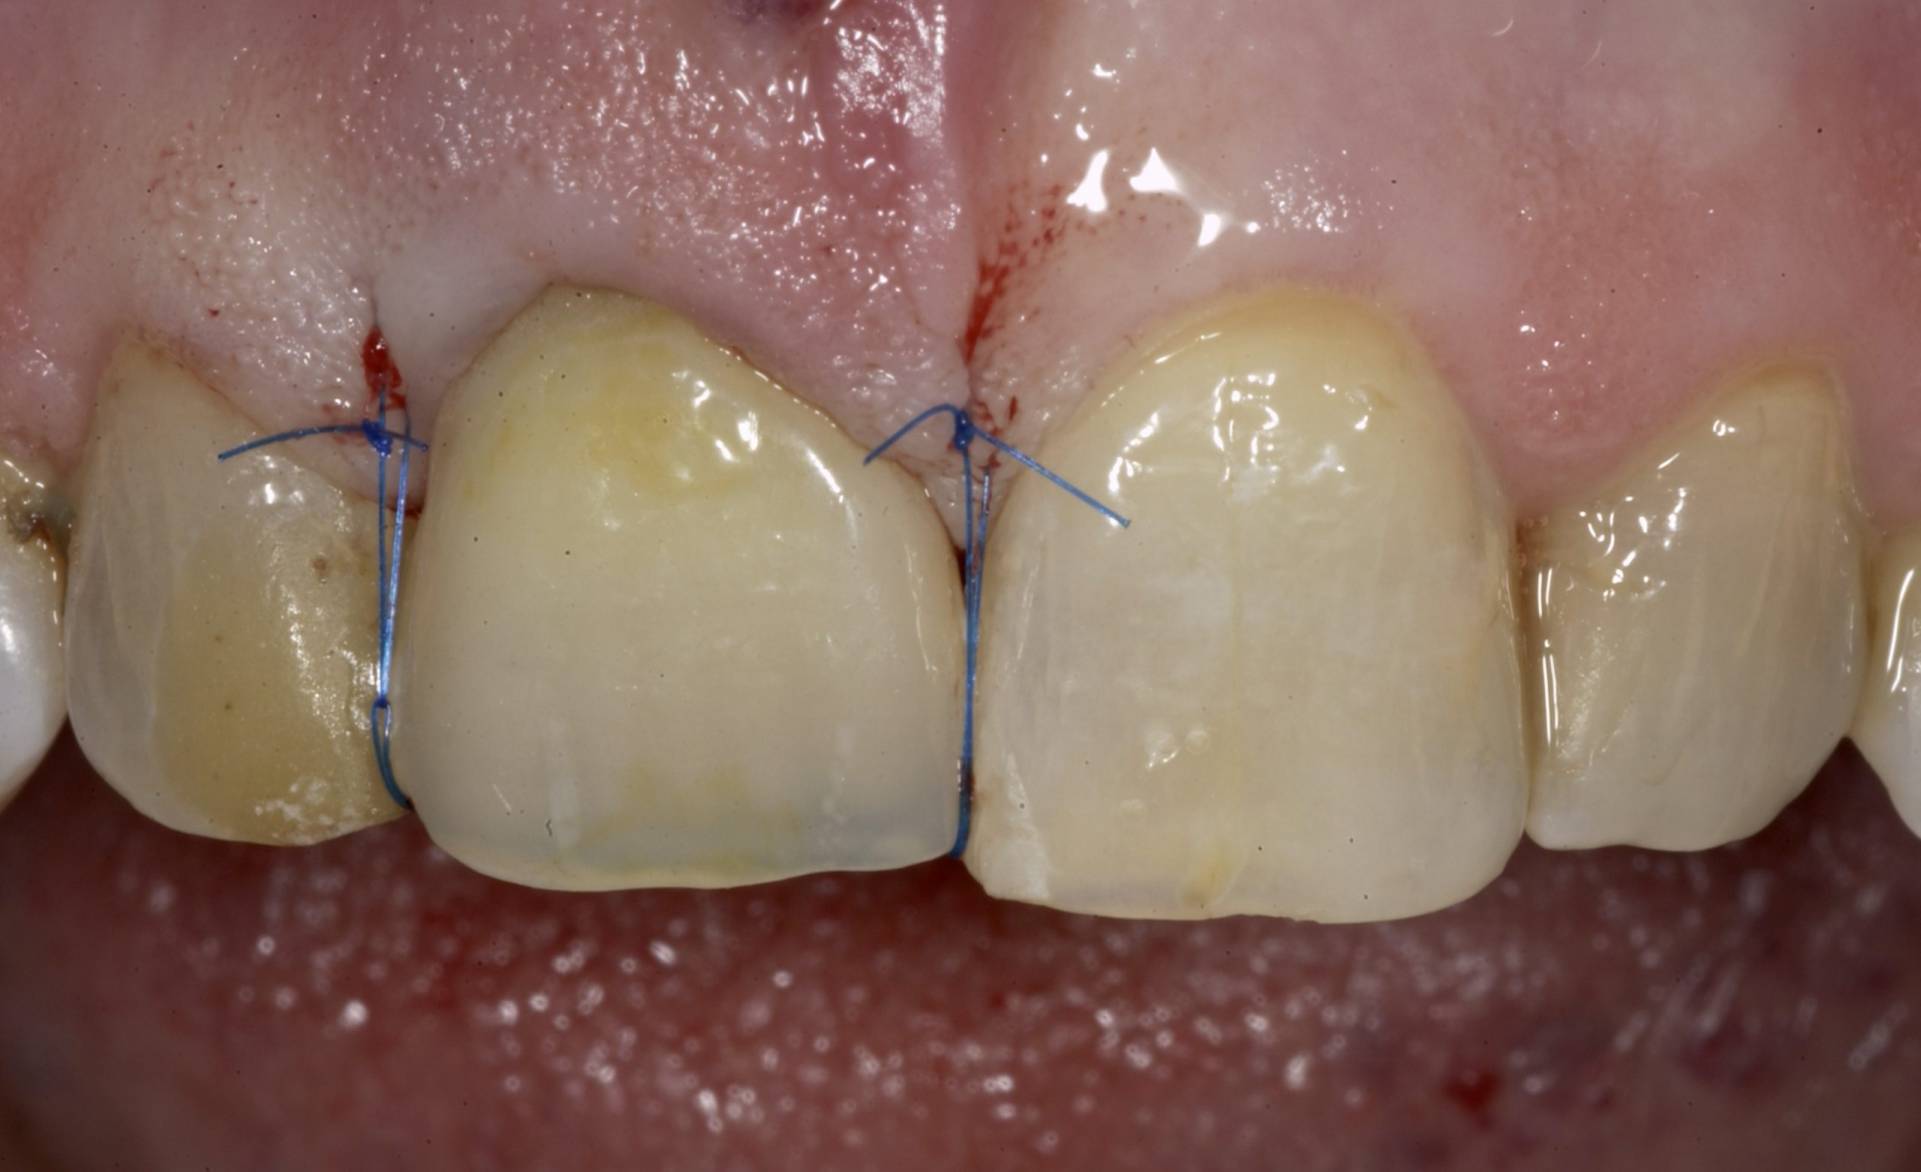

Mithilfe moderner Diagnostik, mikrochirurgischer Techniken und gewebeschonender Verfahren schaffen wir optimale Voraussetzungen für eine sichere Einheilung. Bei Bedarf werden knochenaufbauende Maßnahmen und biologische Regenerationskonzepte integriert, um auch in anspruchsvollen Situationen stabile Ergebnisse zu erzielen.

Das Ziel ist eine funktionell und ästhetisch perfekte Versorgung, die sich harmonisch in das bestehende Gebiss einfügt – für langfristige Stabilität, Sicherheit und ein natürliches Gefühl beim Kauen und Sprechen.